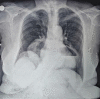

Keywords: Morgagni hernia; Orthopnea; bilateral hernia; dyspnea.